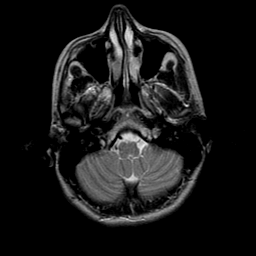

overlay -- Slice #3

[Home][Help][Clinical] Slice 3